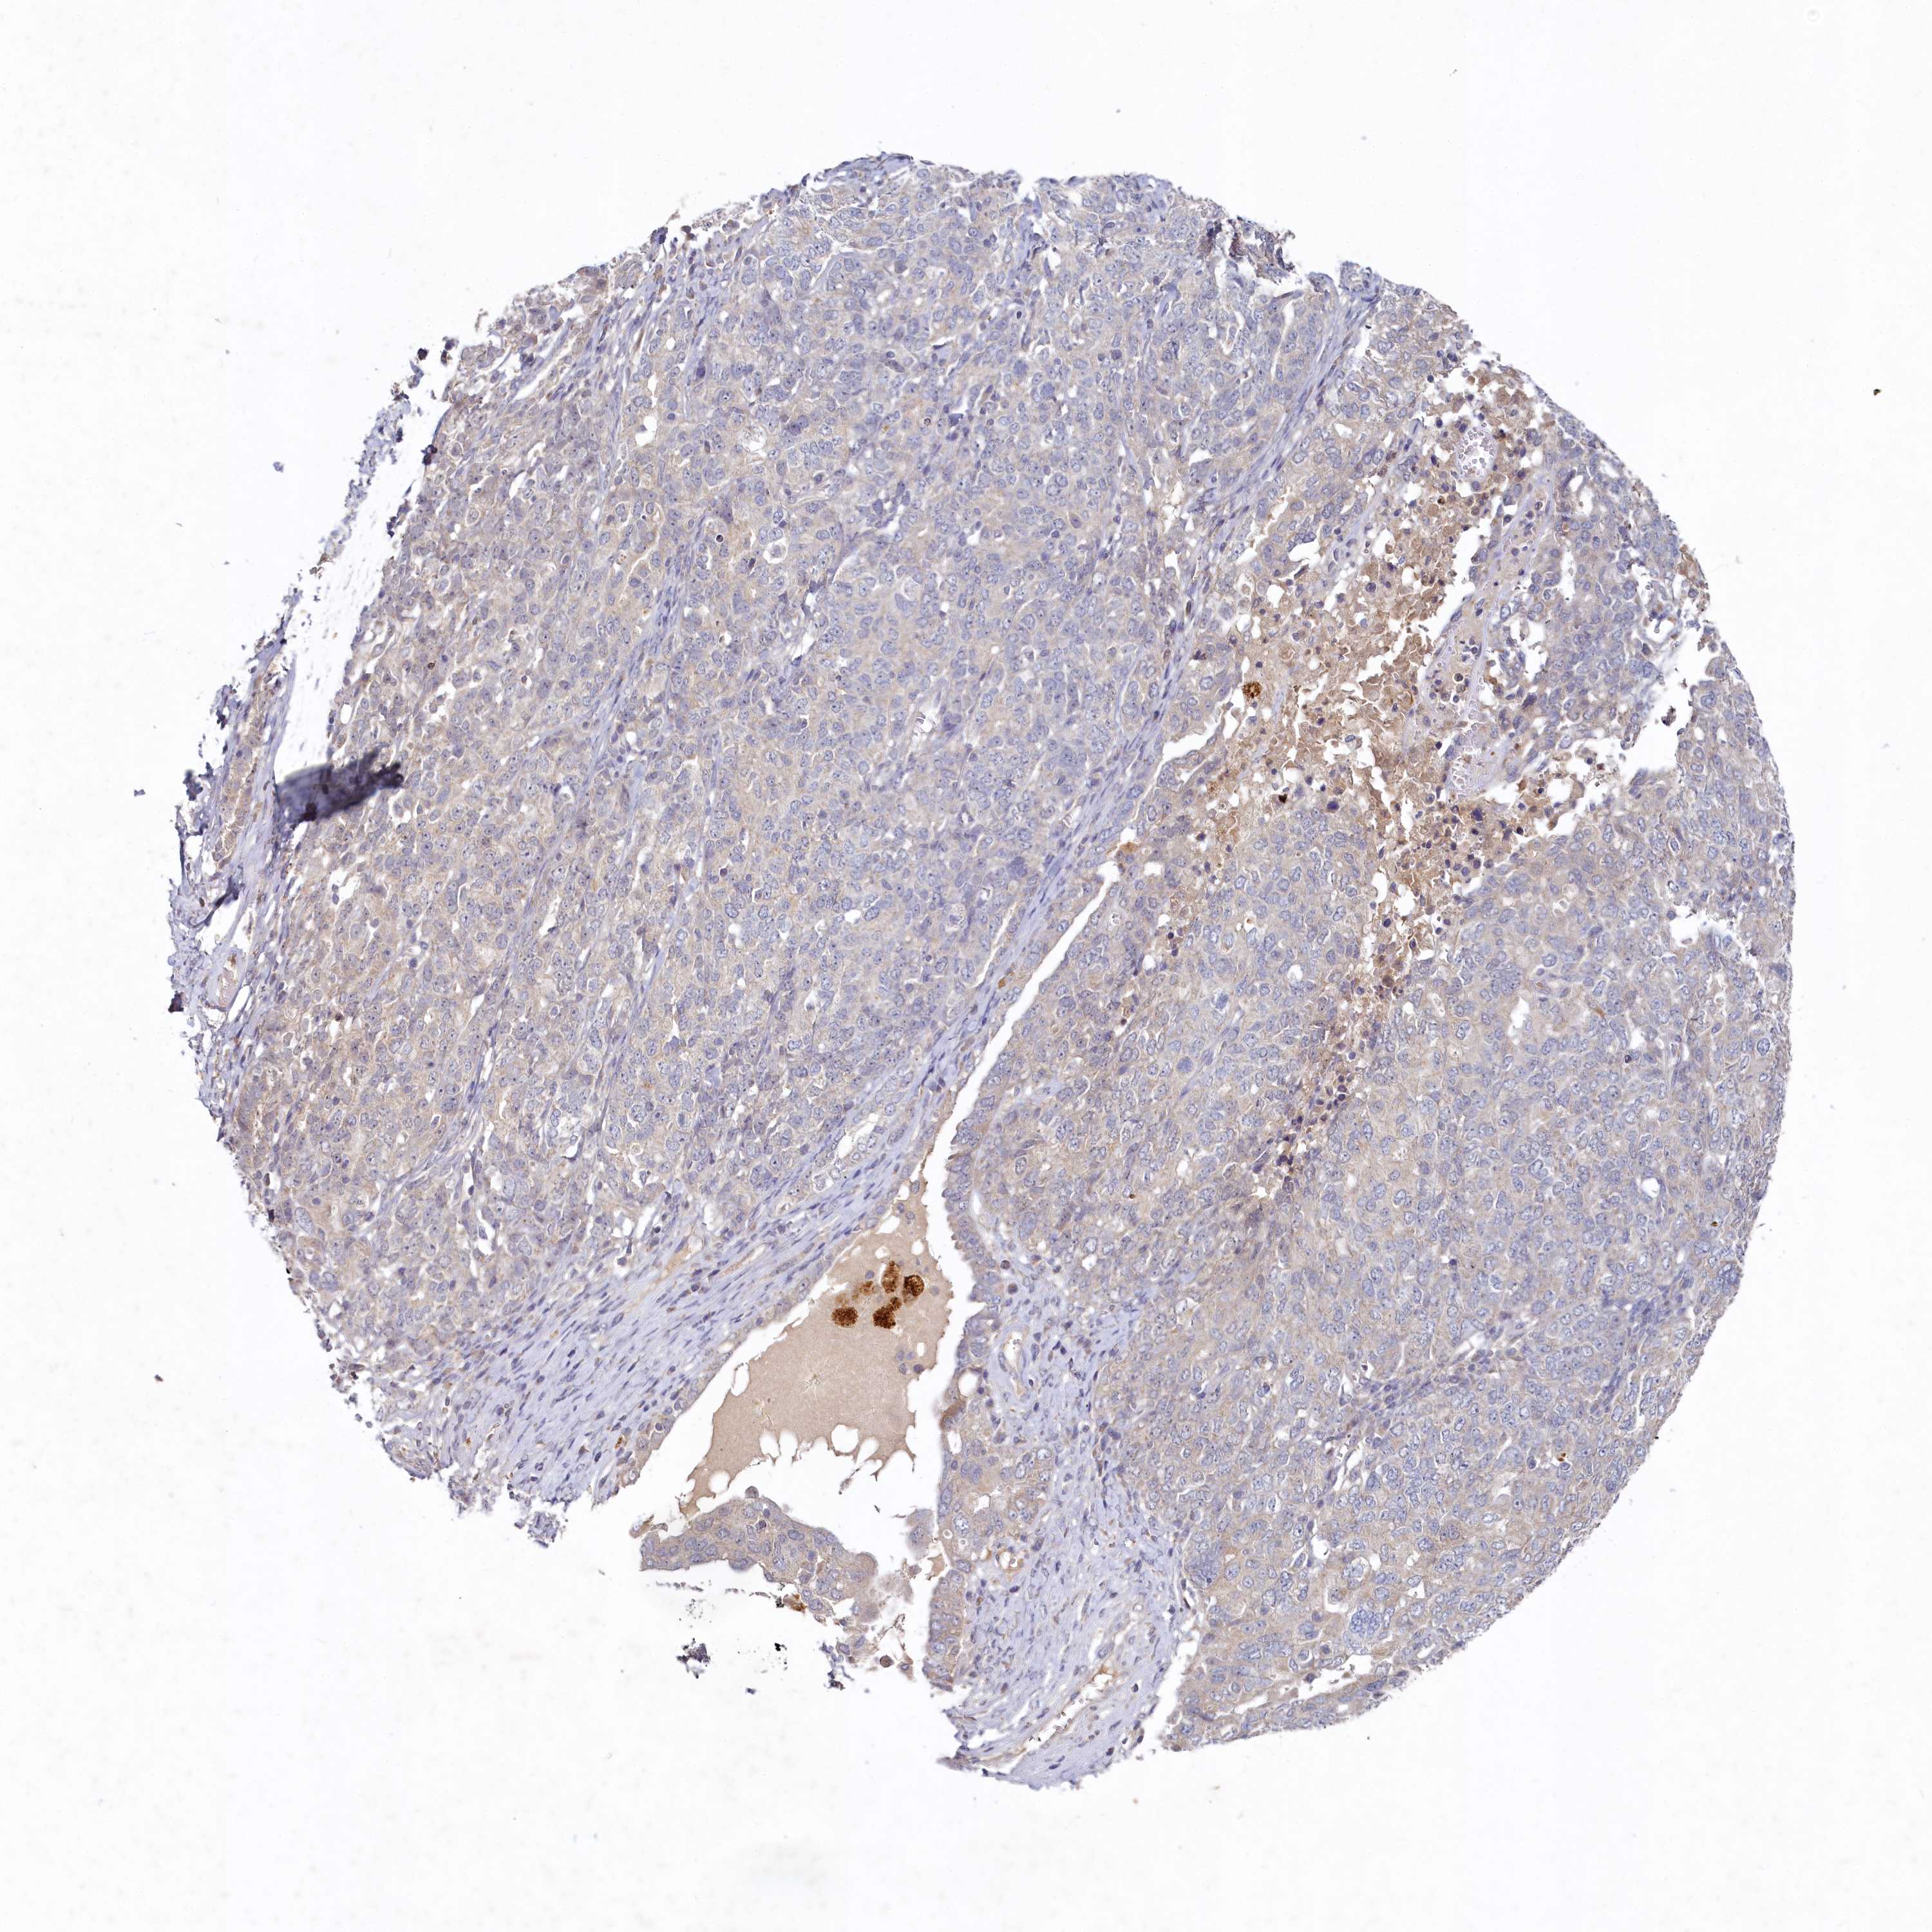

OVARIAN CANCER - Protein expressioni

A mouse-over function shows sample information and annotation data. Click on an image to view it in a full screen mode. Samples can be filtered based on level of antibody staining by selecting one or several of the following categories: high, medium, low and not detected. The assay and annotation is described here.

Note that samples used for immunohistochemistry by the Human Protein Atlas do not correspond to samples in the TCGA dataset.

Antibody stainingi

Antibody staining in the annotated cell types in the current human tissue is reported as not detected, low, medium, or high, based on conventional immunohistochemistry profiling in selected tissues. This score is based on the combination of the staining intensity and fraction of stained cells.

Each image is clickable and will lead to virtual microscopy that enables deeper exploration of all samples and also displays staining intensity scores, fraction scores and subcellular localization as well as patient and tissue information for each sample.

Antibody HPA039170

Staining

High

Medium

Low

Not detected

Intensity

Strong

Moderate

Weak

Negative

Quantity

>75%

75%-25%

<25%

None

Location

Nuclear

Cytoplasmic/membranous

Cytoplasmic/membranous,nuclear

Cystadenocarcinoma, serous, NOS

Carcinoma, endometroid

Cystadenocarcinoma, mucinous, NOS

Carcinoma, NOS